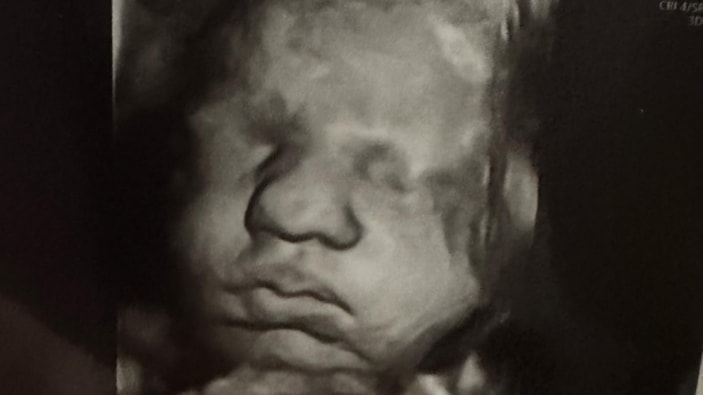

Kelsey Hatcher isimli bir kadın, doğuştan çift rahmi olduğunu ve nadir görülen bir hamilelikle her iki rahminde de kız bebek beklediğini duyurdu.

Hatcher'ın doktoru, genç kadının iki rahminde iki ayrı bebeğe aynı anda hamile kalmasının milyonda bir olduğunu ifade etti.

ABD’nin Alabama eyaletinde yaşayan 32 yaşında, üç çocuk annesi Kelsey Hatcher, uterus didelphys veya iki uterus adı verilen nadir bir uterus anomalisiyle doğdu.

Önceki hamileliklerinde sadece tek bir rahminde bebek taşıyan Hatcher, bebeklerin ikiz mi olacağı konusunda henüz bir bilgi veremediklerini söyledi.